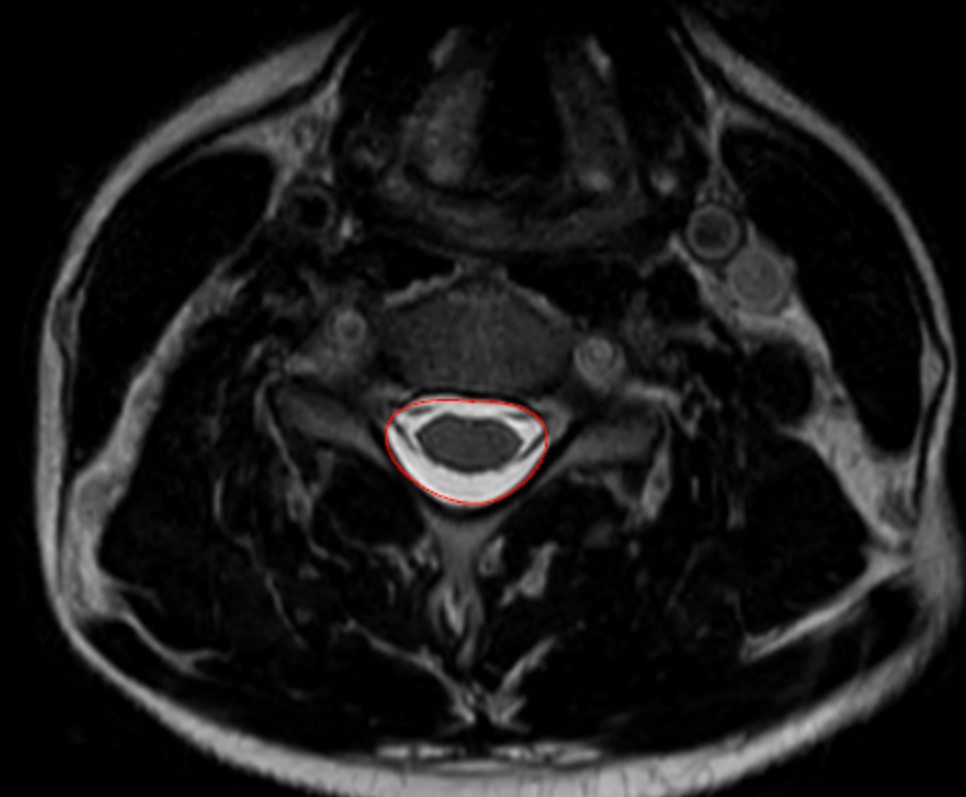

Cross-Sectional Canal Area

1) Description of Measurement

Cross-sectional canal area quantifies the total area of the cervical spinal canal on axial MRI, reflecting the true space available for the spinal cord at a given vertebral or disc level.

Unlike linear measurements (e.g., sagittal canal diameter), canal area accounts for both anteroposterior and transverse narrowing and incorporates soft-tissue contributors such as disc protrusion, ligamentum flavum hypertrophy, and ossification of the posterior longitudinal ligament (OPLL).

Reduced canal area correlates strongly with cervical spinal stenosis, myelopathy, and neurologic risk, making it one of the most physiologically meaningful MRI-based metrics of canal compromise.

2) Instructions to Measure

• Select an axial T2-weighted MRI slice at the level of interest, ideally where stenosis appears greatest (commonly at the disc level rather than mid-vertebral body).

• Identify the bony and soft-tissue boundaries of the spinal canal, including:

• Posterior vertebral body or disc-osteophyte complex (anterior boundary)

• Pedicles and laminae (lateral boundaries)

• Ligamentum flavum (posterior boundary)

• Using a freehand region-of-interest (ROI) tracing tool on PACS:

• Carefully trace the inner margin of the spinal canal, following the boundary of the thecal sac and excluding epidural fat and bone.

• Close the ROI to generate an automated area calculation (mm²).

• Repeat at adjacent levels if needed and record the smallest canal area, as this represents the level of maximum stenosis.